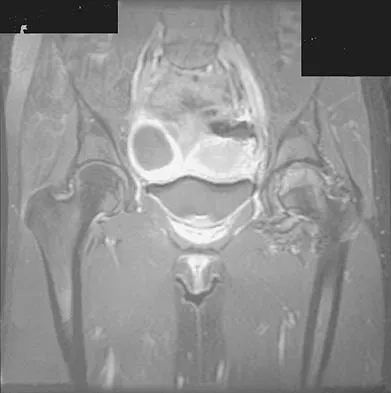

Figures 1a through 1c show the radiograph and MRI scans of a 16-year-old patient who has a painful hip. Examination reveals a significant limp, limited abduction and internal rotation, and severe pain with internal rotation and adduction. A biopsy specimen is shown in Figure 1d. What is the deposited pigment observed in this condition?